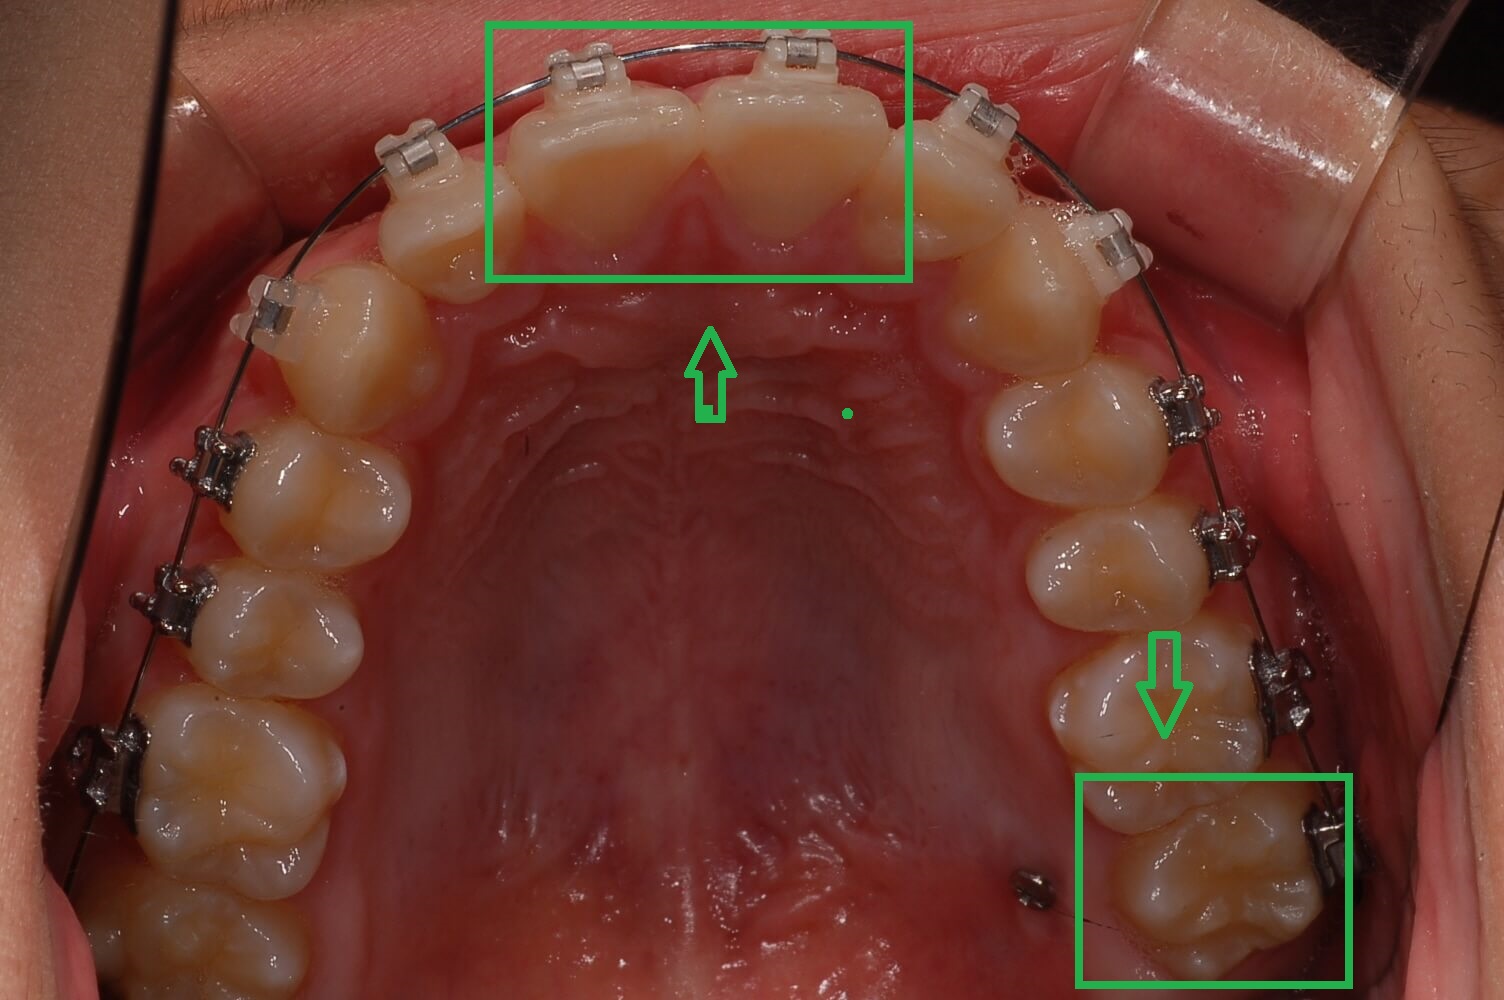

3. 가위교합 + 과개교합 교정실시 (전체브라켓 부착)

3개월간 가위교합 교정이 들어갔고 어느 정도 어금니가 제자리로 돌아왔습니다. 과개교합 교정을 위해 전체브라켓을 부착 하고 있는 사진입니다.

사진에 보면 철사가 S자 모양으로 휘어져 있습니다. 이 철사가 일자형으로 복원이 되면서 틀어진 치아배열을 정돈한다고 하는데 정확한 전문지식은 아니니 참고만 해주세요.

▼ 어금니 교정 후 전체 브라켓 부착